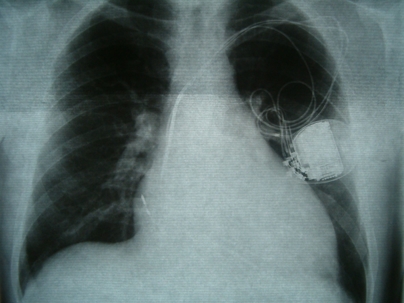

Heart Pump Implant

A heart pump implant called the HeartWare Ventricular Assist Device, or HVAD was meant to give patients time to find transplants. It was first introduced into the U.S. market in 2012.